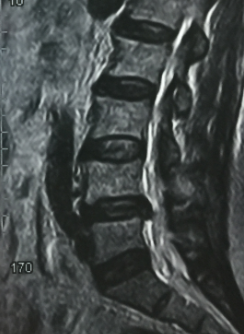

比如家住城关镇的石先生,因4个月前在家里搬煤气瓶后突然出现腰痛及左下肢疼痛,疼痛由左臀部放射到小腿后侧,疼痛剧烈,不能站立及行走,严重影响日常生活。他到处就医,针灸、推拿、中药等各种方法都试了,钱花了不少,腰痛及下肢酸痛麻木丝毫没有改善。3月1日石先生来我院就诊,门诊查体腰椎MRI显示腰椎间盘巨大突出,压迫神经根。董永强主任详细询问病史并通过仔细的检查,决定为石先生实施椎间孔镜下髓核摘除微创手术。